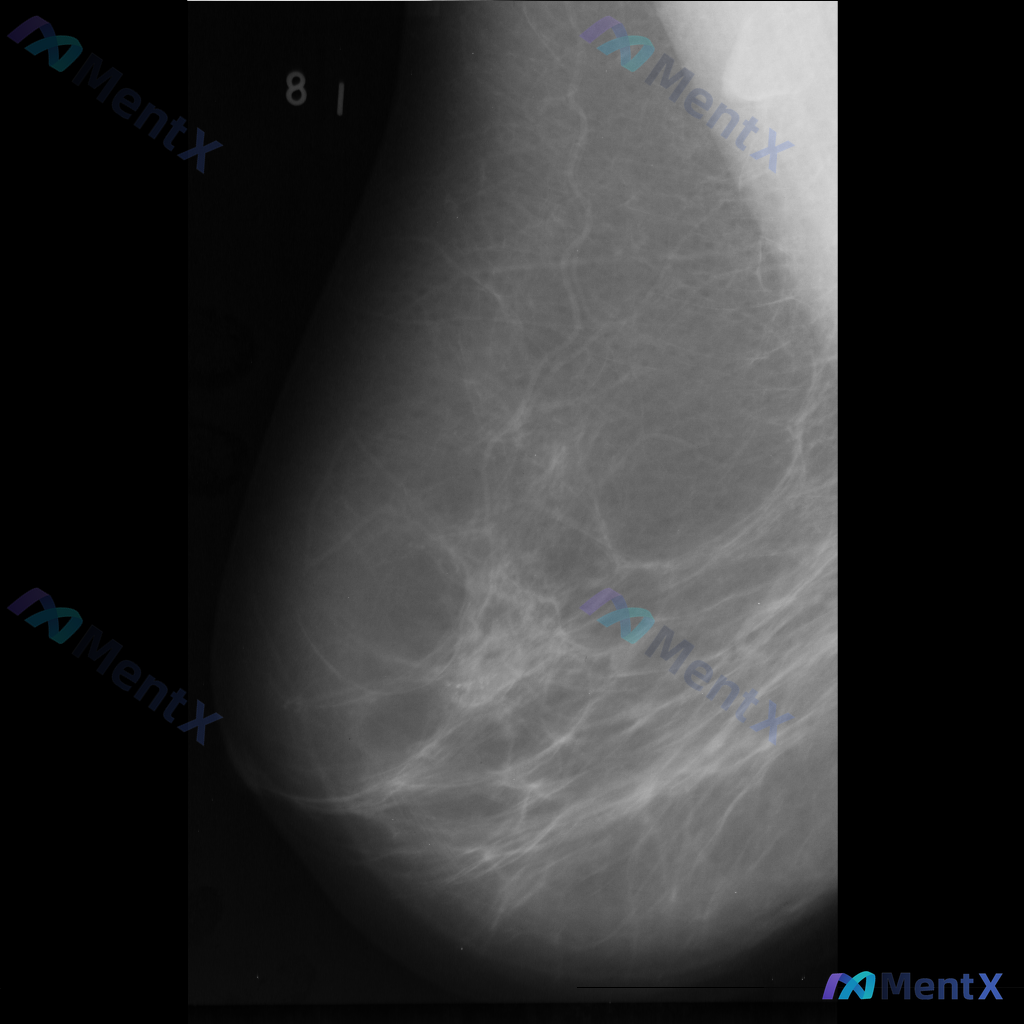

整理到一份乳腺钼靶影像资料,主要异常表现如下: - 部位:乳腺中部偏下方 - 影像征象:局灶性不规则腺体密度增高,伴结构扭曲 - 背景:致密型乳腺 目前仅单张影像资料,未提供其他体位、超声或临床病史。 想和大家讨论一下:单看这组异常表现,你会先往哪个方向考虑?后续如果要进一步明确,你觉得优先做什么检...